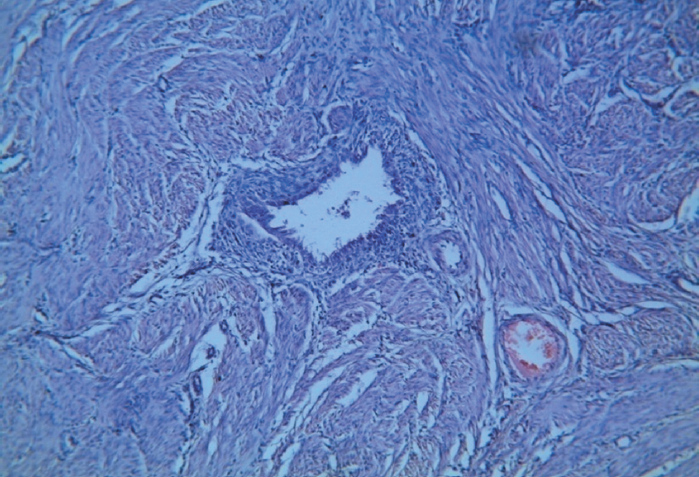

- Лейомиомы с очагами эндометриоза (рис. 4, 5). 2. Очаги эндометриоза между пучками гладкомышечных волокон (рис. 3). 3. Лютеиновая киста яичника.

Рис. 4. Очаг эндометриоза в лейомиоматозной ткани с преобладанием стромального компонента. Окраска гематоксилином и эозином. Увеличение ×10

Fig. 4. Endometriosis foci within leiomyomatous tissue with a predominant stromal pattern. Haematoxylin and eosin stained specimens. ×10 magnification